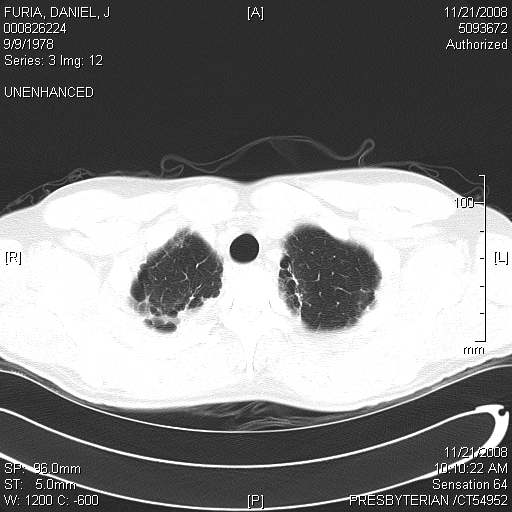

"Blebs" are weak spots that form at the top of the lung. These weak spots can leak air and cause a lung to collapse. This image shows dozens of small blebs on each of my lungs. This cat scan image was taken from above, looking down on to the top of the lung. (In other words try to imagine that you are floating up above me, looking down at the top of my head. If you could see layer by layer into my body, like the CT scan, you would then eventually see the tops of my lungs). The big dark black circle in the middle of the image is my windpipe.